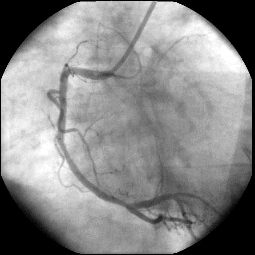

For the first patients, we obtained a good agreement in terms of stenosis diagnosis between synchrotron angiography and the usual angiography procedure in hospital. One image obtained with the first patient at the ESRF is shown on Figure 1a. Stenosis appears visible inside the stent in the second segment C2, and the known distal stenosis visible at the crux remains mild (inferior to 50%). We stress the excellent visualization of the distal part of the right coronary artery (RCA). These findings were in excellent agreement with the conventional selective coronarography perfomed few hours later in the hospital cardiological unit (Figure 1b).

a: Intravenous synchrotron angiogram of the first patient at the ESRF taken in a left anterior oblique (LAO) projection. The image shows the second segment C2 with a stent and the crux. RCA: right coronary artery.